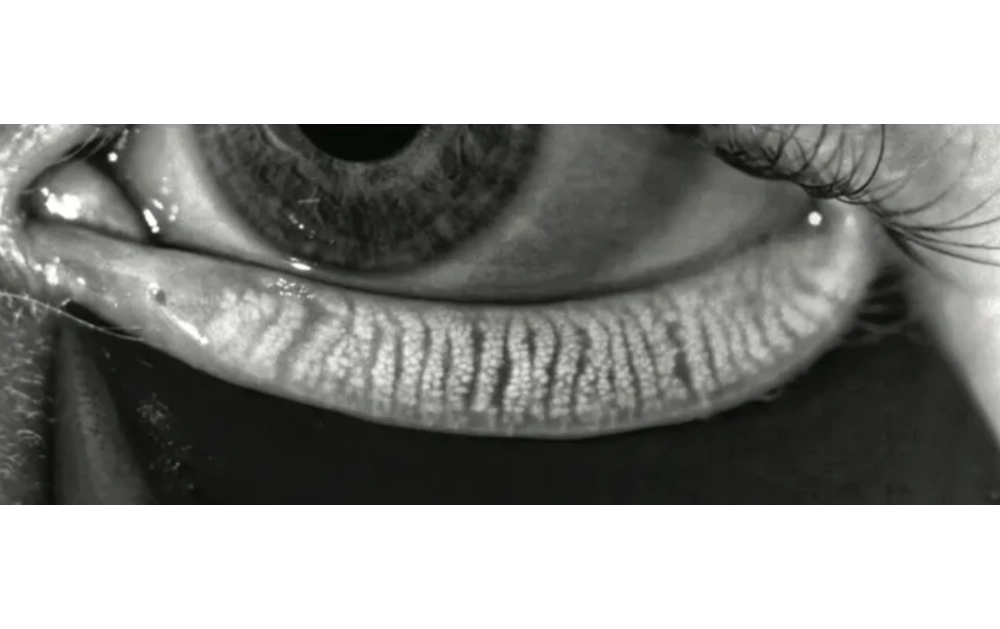

A specialized infrared camera captures images of the inner eyelid to assess gland structure.